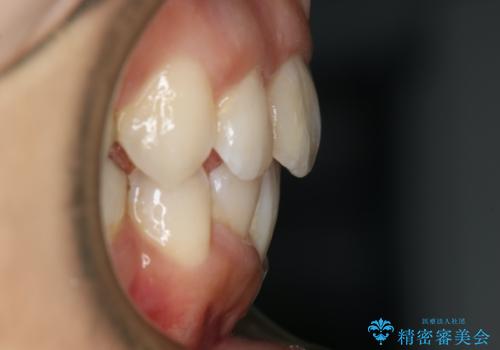

出っ歯が気になる 抜歯+ワイヤー矯正治療

- 歯のガタつきと出っ歯が気になるので矯正治療を希望し来院された患者様です。

上下顎とも歯を並べられるスペースが無く、口元を下げたいというご希望だったので、抜歯とワイヤー矯正を併用した治療を計画しました。

抜歯スペースを利用し口元を大きく下げることが出来ました。